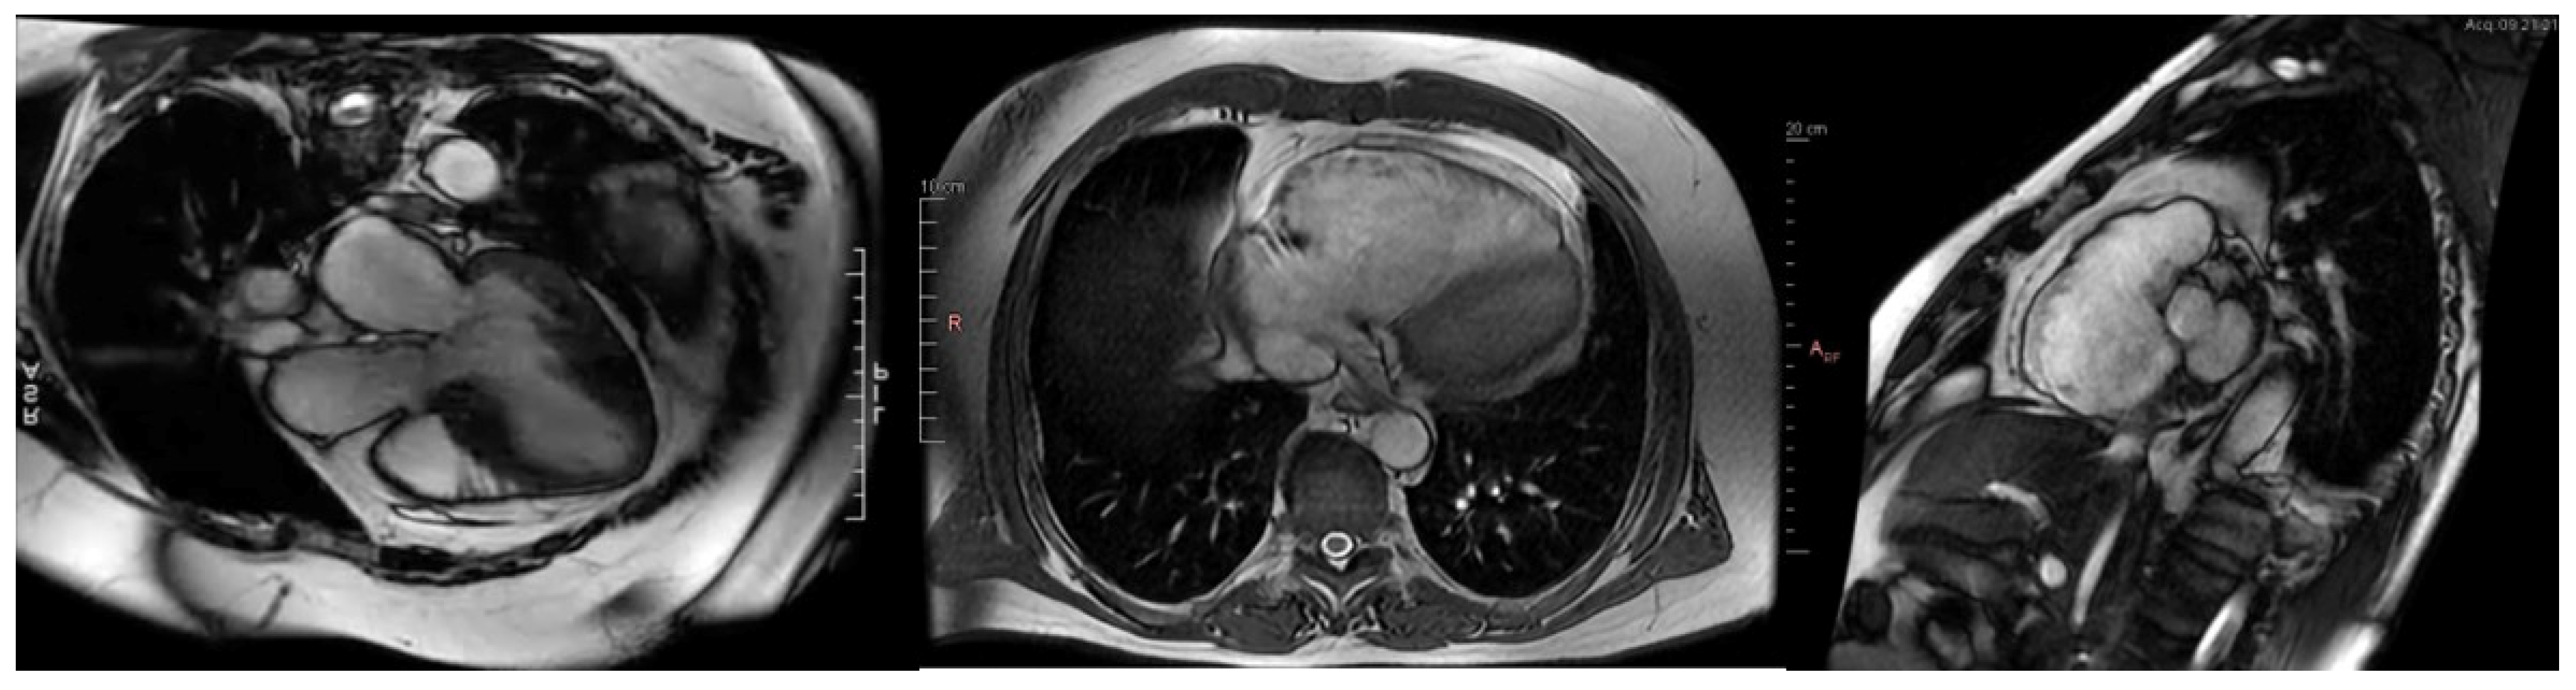

2.2. Cardiac Magnetic Resonance Imaging: Gold Standard

- Licordari, R.; Trimarchi, G.; Teresi, L.; Restelli, D.; Lofrumento, F.; Perna, A.; Campisi, M.; de Gregorio, C.; Grimaldi, P.; Calabrò, D.; et al. Cardiac Magnetic Resonance in HCM Phenocopies: From Diagnosis to Risk Stratification and Therapeutic Management. J. Clin. Med. 2023, 12, 3481. [Google Scholar] [CrossRef] [PubMed]